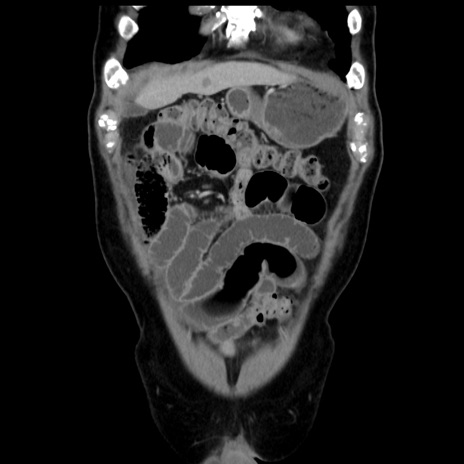

症例16(冠状断像)

【症例】 70歳代男性

【主訴】 腹痛、嘔吐

【現病歴】 約1ヶ月前より間欠的に腹痛と嘔吐あり、当院消化器内科を受診したところCTで多発する肝臓のLDAを指摘され、精査中であった。以降は消化器症状は安定していたが、2日前より嘔気と腹痛があり、同日より排便・排ガスが消失した。改善認めず、 本日、救急外来を受診した。

【既往歴】 大腸ポリープ切除後。

【身体所見】意識清明・会話良好、BT 36.3℃、BP 127/80mmHg、 P 80bpm、腹部:膨満あり、平坦・軟、上腹部正中および下腹部正中に圧痛あり、反跳痛なし、筋性防御なし。

【データ】WBC 7200、CRP 0.77